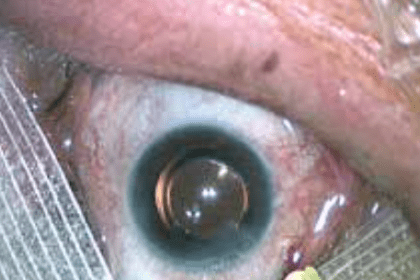

Glaucome : Les facteurs de risque

Le glaucome se caractérise par une détérioration progressive du nerf optique. La…